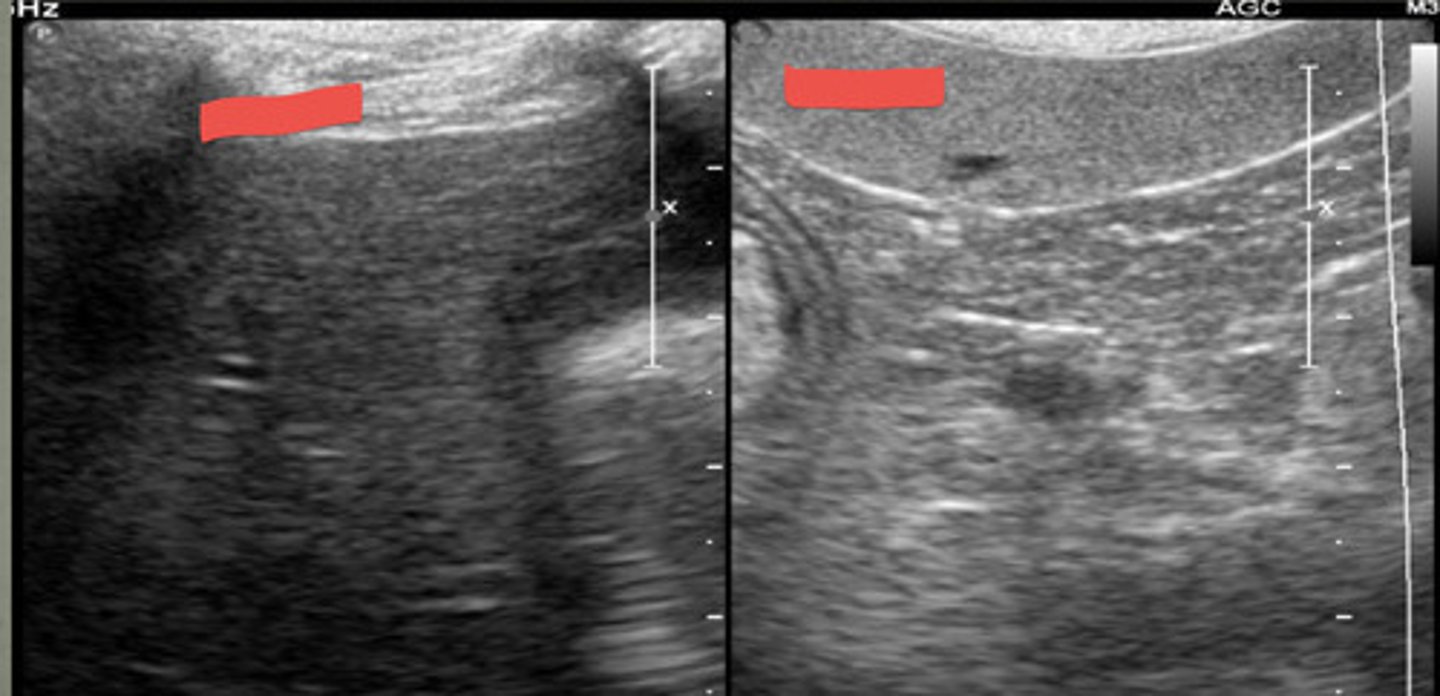

focal

are these ultrasound images of the spleen focal or diffuse?

diffuse

are these ultrasound images of the spleen focal or diffuse?